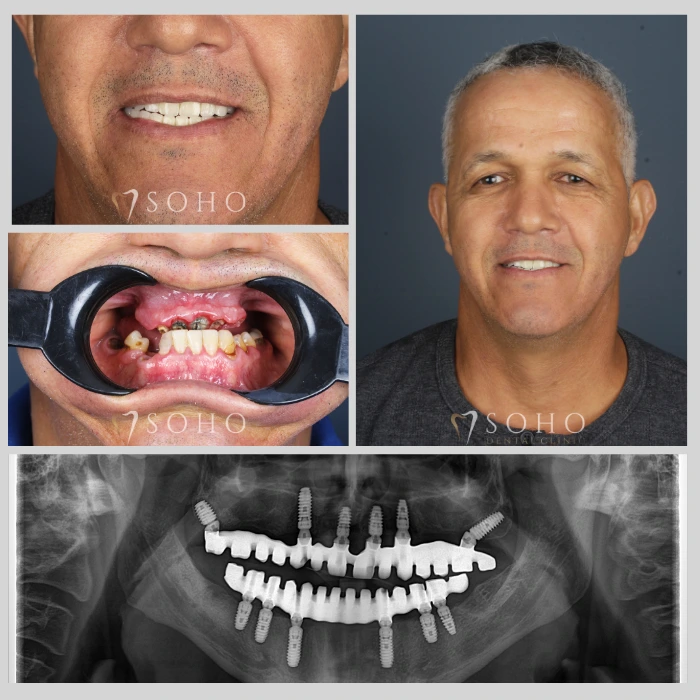

Real Patients. Real Smiles.

Explore the journey of our international patients through authentic visuals, elegant transformations, and moments captured inside Soho Dental Clinic. Let their stories inspire your own.

From First Visit to Final Smile.

Explore real patient stories captured in every transformation. These are more than smiles — they are renewed confidence, achieved with care and precision at Soho Dental Clinic.